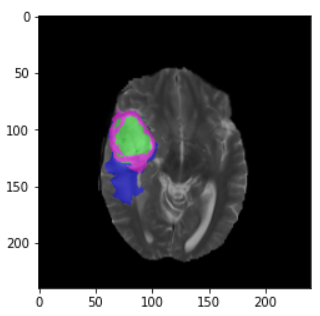

plt.imshow(nda[n, :, :]) # n为要读取的切片

plt.imshow(nda1[n, :, :]) # n为要读取的切片